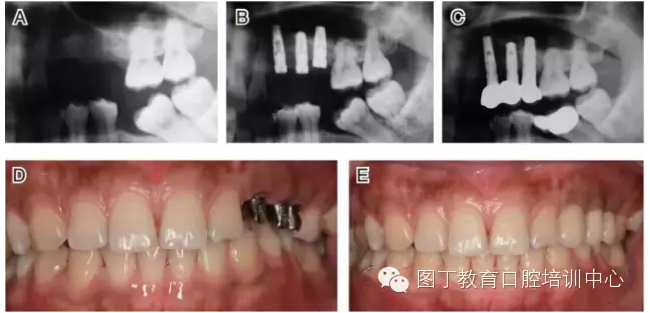

病例5 多顆種植體(圖7)

圖7

病例8 多顆種植體植入(圖10)

圖10